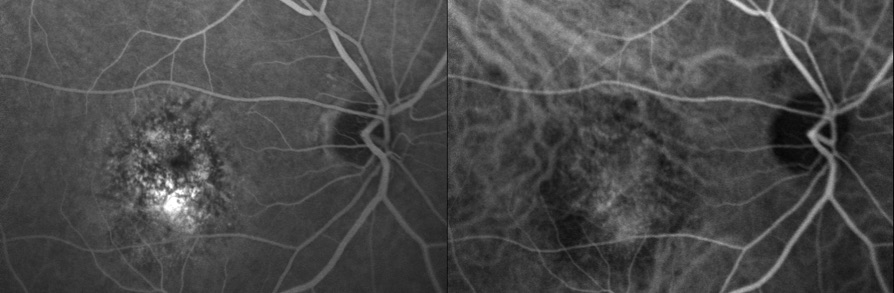

The next series of studies published explored what happend to the subfoveal nets (SRNVM) if not treated. Some found the natural history of very poor outcomes and suggested that sacrificial laser to the fovea may limit the size of the disceform scar that would develop. Many had a problem with the idea to sacrifice the fovea in this case and would not do it. Others decided to do a “Ring laser”, a treatment ring of laser placed just outside the central SRNVM that would try to limit the spread of the foveal SRNVM. This would also limit the elevation of the macula away from the choroid due to the forming the disceform process. In practice, some patients maintained 20/100-200 vision with clearly reduced leakage of the central SRNVM on the fluorescein angiogram after Tx. There were some regaining 20/30-40 vision achieving driving status again. These visions were maintained for many years after treatment. There were a few others that would continue to scar to CF vision dispite all efforts. When Photodynamic therapy was announced, theoretically it should be superior to ring laser and ring laser fell by the wayside.

The announcement of the photodynamic therapy (PDT) system with the low power “cold laser” illuminating the macula to activate the chemotherapeutic drug injected in the vein of the patient seemed to be an answer to every suffering patient with a foveal SRNVM. What was not known until later was that the treatment would increase the production of vascular endothelial growth factor (VEGF) and as a result, there were many reoccurrences of the SRNVM. More treatments of PDT seemed to control the problem up to 5 treatments. At that time any patient that fit the rather limited criteria for treatment was sent to Raleigh to get the treatment rather than the ring laser. Later analysis showed that most of these patients achieved CF vision with a very large atrophic scar centrally about the same size as what would have been the result of no treatment namely a disceform scar with the same vision. This was much poorer that the results of the ring laser. No real advantage to this treatment long term and PDT has mostly fallen out of favor.